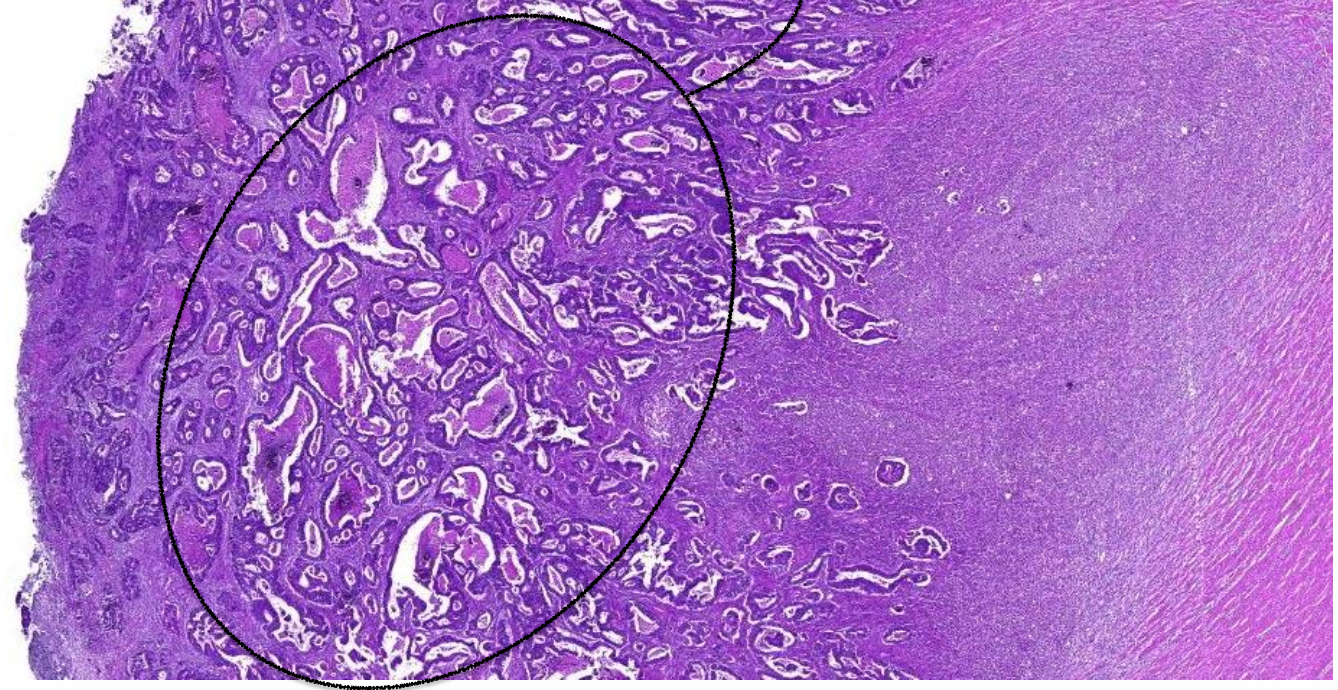

welk orgaan

prostaat hypertrofie

pathologische kenmerken prostaat hypertrofie

ipv lobulaire—> nodulaire indeling, omgeven door bindweefsel

bevat gedilateerde klierbuizen

vorming van cysten (cysteuze dilatatie)

toename stroma, glad spierweefsel en lymfocyten